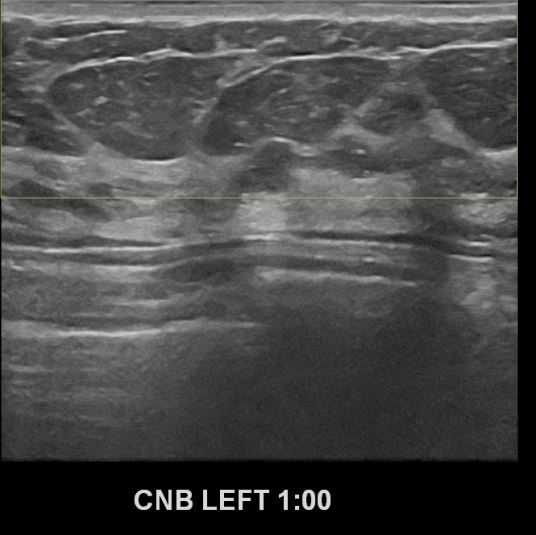

상기환자 2018년 4월에 멍울만져져 처음내원하신분으로 본원에서 우측 조직검사시행후

유방암진단되어 3차병원의뢰드린 환자입니다. 추적관찰중 좌측에 의심스러운혹 있어

조직검사시행후 좌측유방암 진단되었습니다.